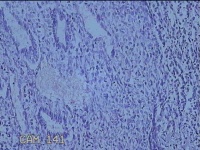

宫腔内容物

性别

女

年龄

47岁

临床诊断

1.异常子宫出血 2.慢性宫颈炎

一般病史

不规则阴道流血21天。

标本名称

大体所见

灰白暗红色不规则碎组织2.5x1.8x0.3cm一堆。

图1